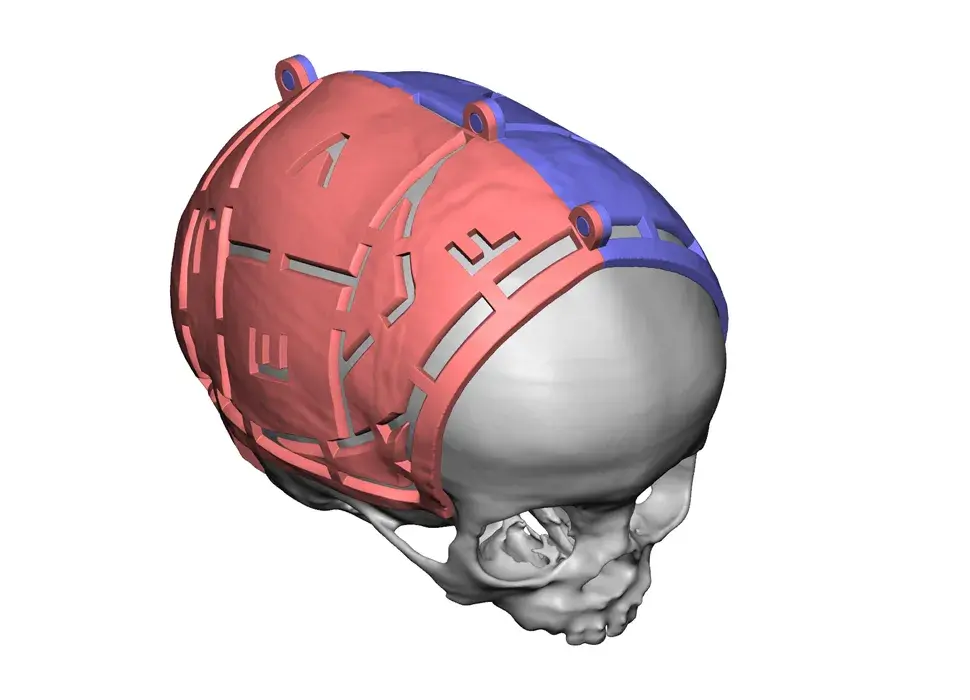

3D Systems' VSP® surgical planning solutions for craniomaxillofacial (CMF) applications received FDA clearance as a service-based approach to personalized surgery over 10 years ago.

3D Systems and Stryker Corporation have partnered to provide surgeons with best-in-class products and services for craniomaxillofacial surgeries. As a leader in personalized healthcare solutions, 3D Systems has planned and delivered devices for more than 140,000 patient-specific cases. The Stryker Craniomaxillofacial business specializes in providing patient-specific options and innovative solutions that help drive efficiencies in surgical suites. The combination of Stryker’s specialized team and advanced implants with 3D Systems' cutting-edge 3D printing technologies and expert consulting services positions both companies to provide a superior level of service to healthcare professionals who use these revolutionary solutions.